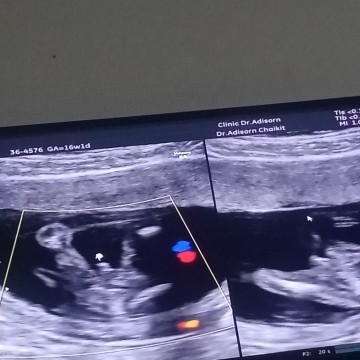

ตัวแสบยังอยู่ในท้องอยู่เลย